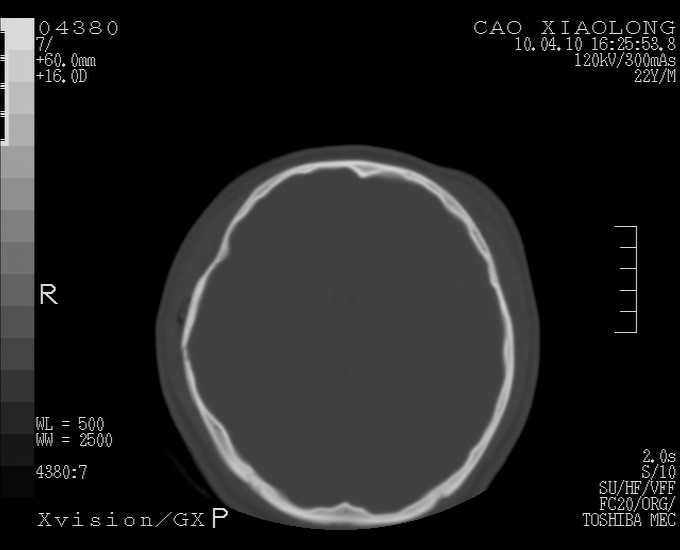

以下是引用随光逐影在2010-4-11 11:00:00的发言:[br]1)左侧额颞顶部硬膜下血肿。2)蛛网膜下腔出血。3)右侧颞顶部颅骨线形骨折。[br][br]20小时后复查:左侧额颞叶脑挫裂伤;左侧额颞顶部硬膜下血肿及蛛网膜下腔出血有吸收表现;右侧颞顶部颅骨线形骨折。[br]